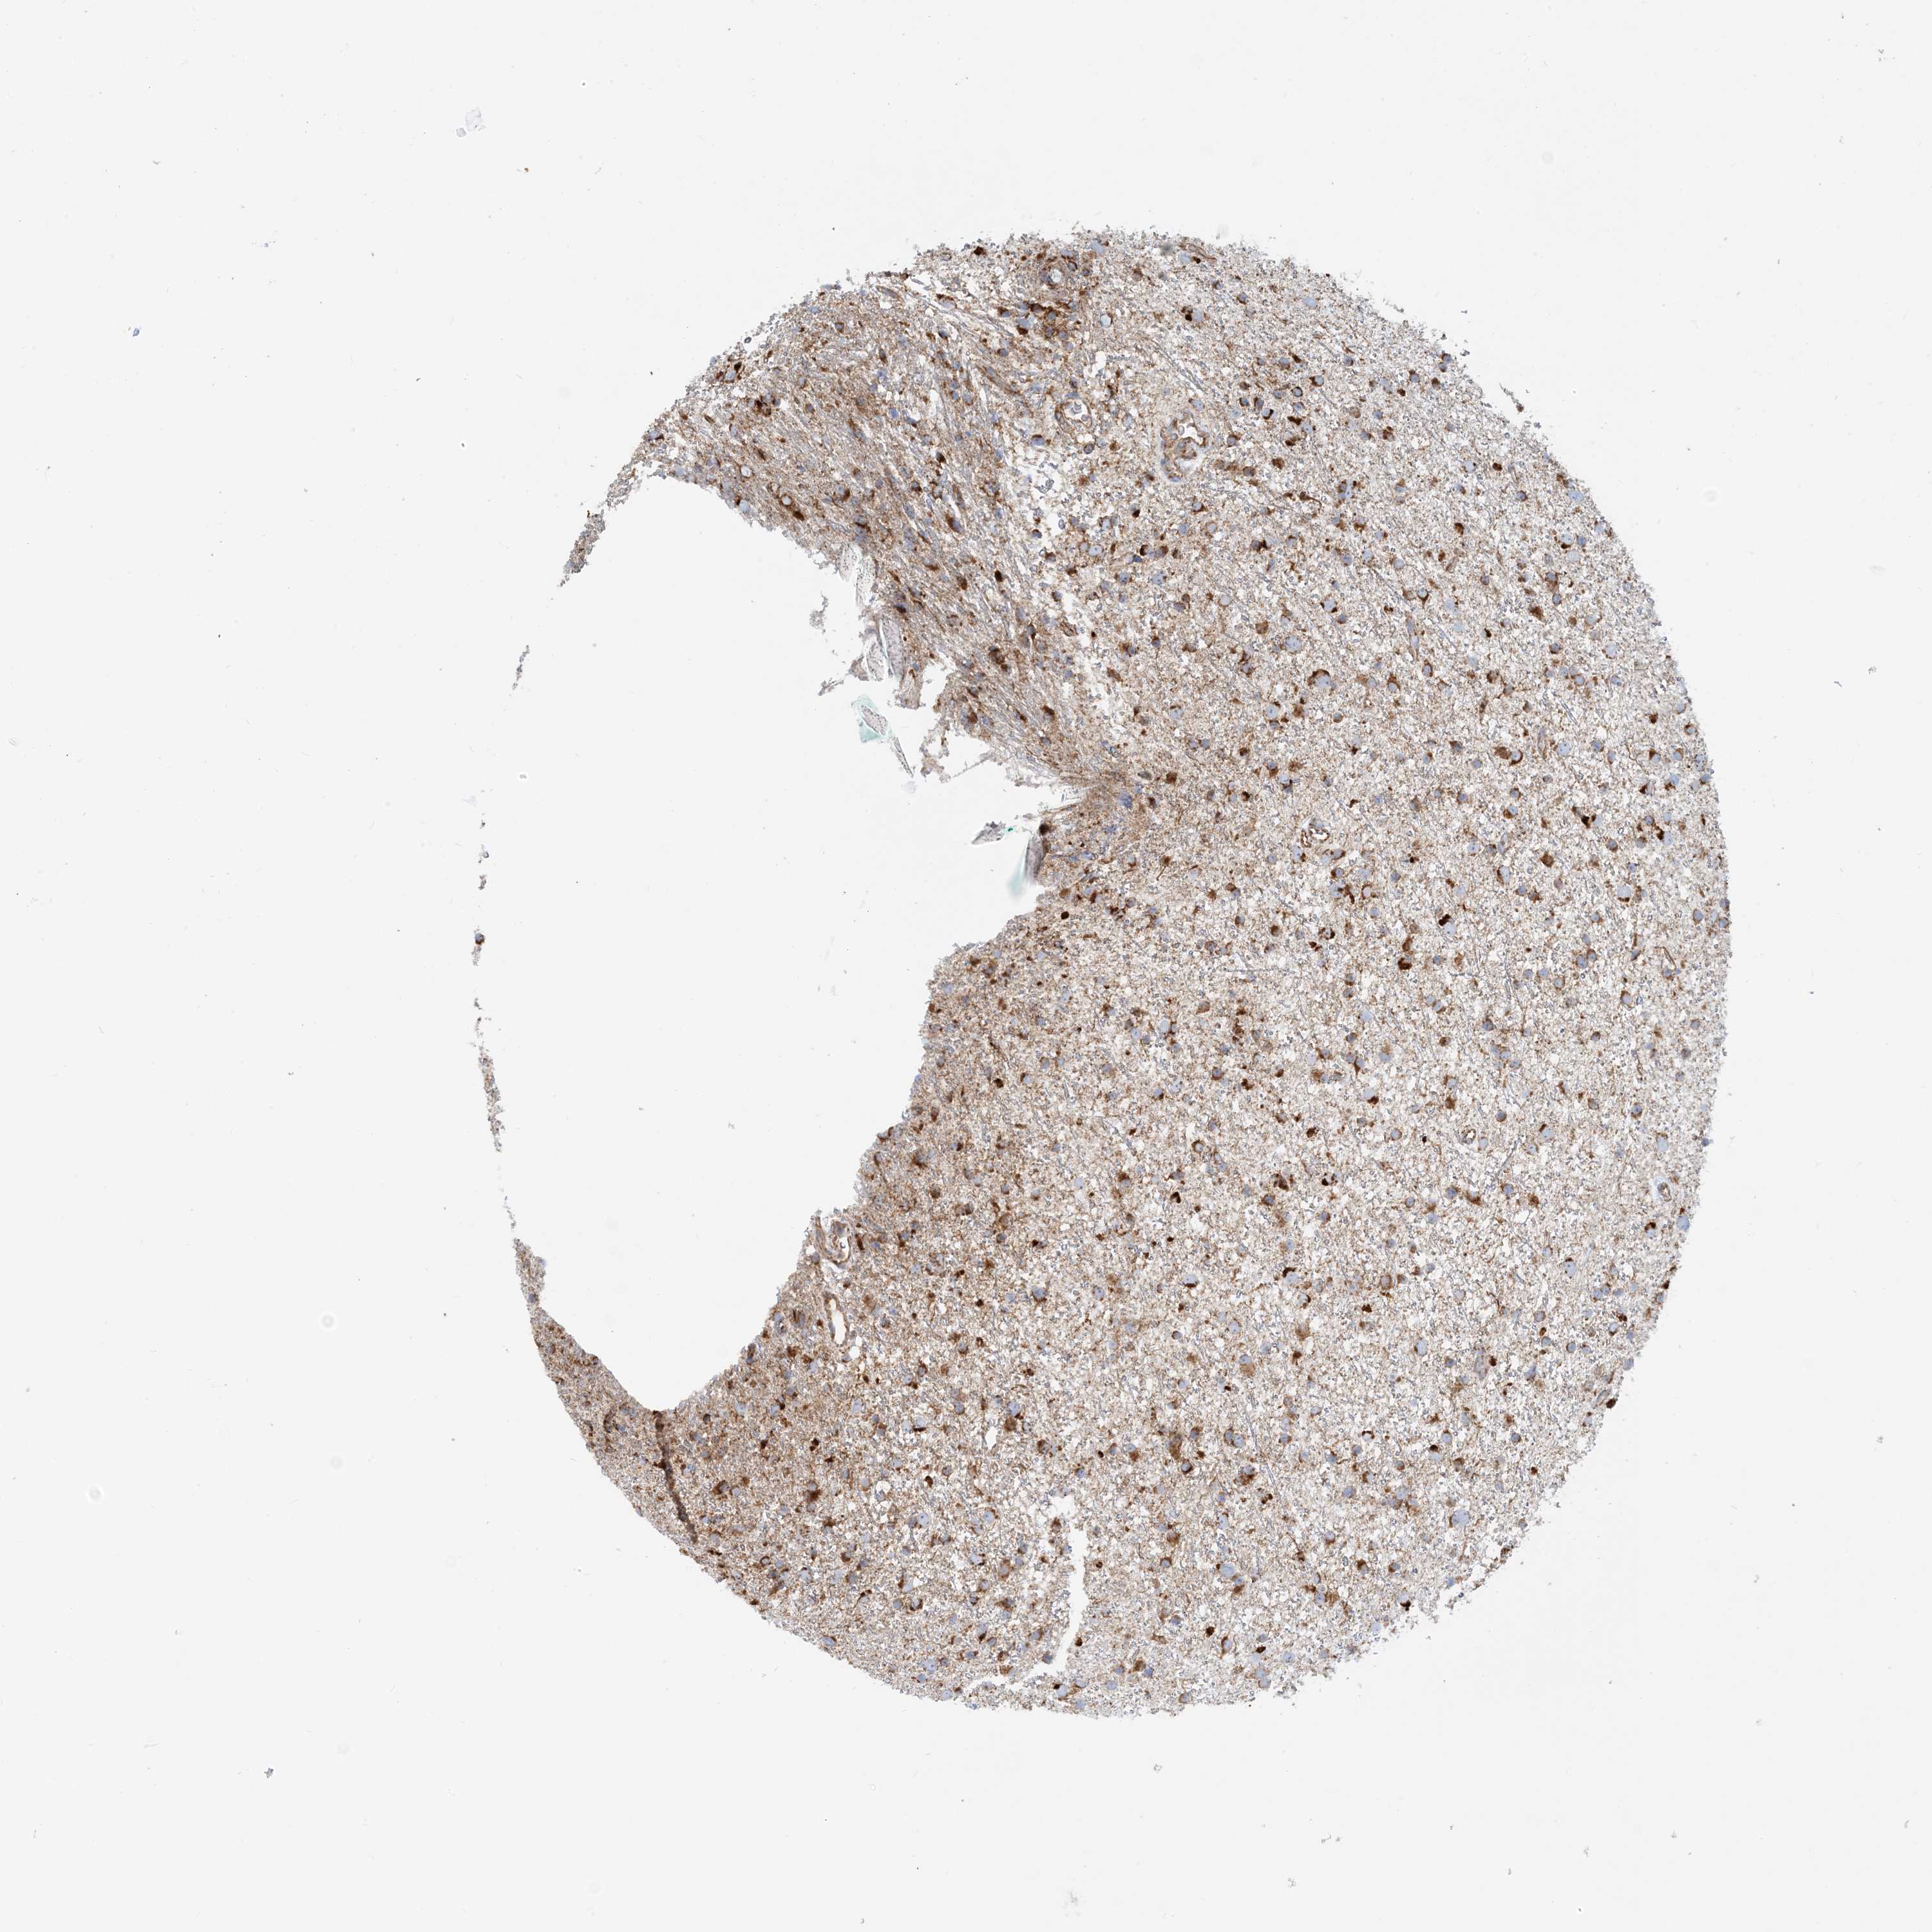

GLIOMA - Protein expressioni

A mouse-over function shows sample information and annotation data. Click on an image to view it in a full screen mode. Samples can be filtered based on level of antibody staining by selecting one or several of the following categories: high, medium, low and not detected. The assay and annotation is described here.

Note that samples used for immunohistochemistry by the Human Protein Atlas do not correspond to samples in the TCGA dataset.

Antibody stainingi

Antibody staining in the annotated cell types in the current human tissue is reported as not detected, low, medium, or high, based on conventional immunohistochemistry profiling in selected tissues. This score is based on the combination of the staining intensity and fraction of stained cells.

Each image is clickable and will lead to virtual microscopy that enables deeper exploration of all samples and also displays staining intensity scores, fraction scores and subcellular localization as well as patient and tissue information for each sample.

Antibody HPA031966

Staining

High

Medium

Low

Not detected

Intensity

Strong

Moderate

Weak

Negative

Quantity

>75%

75%-25%

<25%

None

Location

Nuclear

Cytoplasmic/membranous

Cytoplasmic/membranous,nuclear

Glioma, malignant, High grade

Glioma, malignant, Low grade

Glioblastoma, NOS